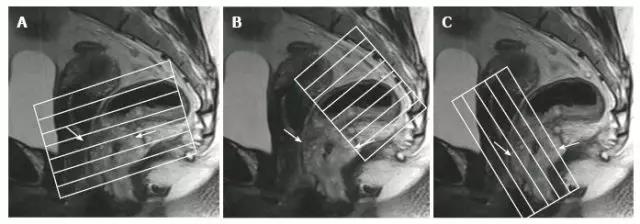

直肠癌的多学科诊疗模式包括术前新辅助放化疗和 TME 手术,增加了对局部进展期肿瘤的局部控制,成为直肠癌的标准治疗方法。高分辨率盆腔磁共振成像(MRI)是直肠癌分...